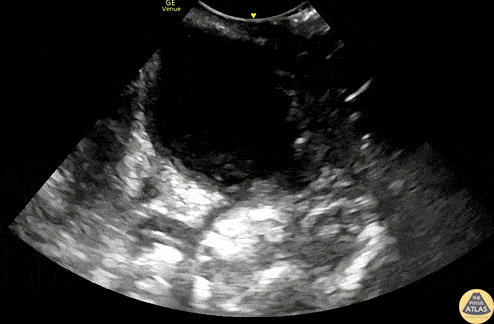

A 20s F with PMH of prior peritonsillar abscess presented with about 1.5 weeks of sore throat, and had been maintained on oral antibiotics with no improvement. Her PCP identified a PTA on clinical exam and referred her to the ED for drainage. This US clip demonstrates the peritonsillar abscess, with an area of hypoechoic, heterogeneous fluid. Posteriorly (far field or bottom of image), the carotid artery is seen pulsating. US in preparation for PTA I&D is particularly helpful in determining the size of the abscess and location of the carotid artery, allowing proper measurement of the plastic guard on the aspiration needle, to prevent inadvertently deep puncture. Dr. Michael Heffler, PGY3 Denver Health Residency in Emergency Medicine